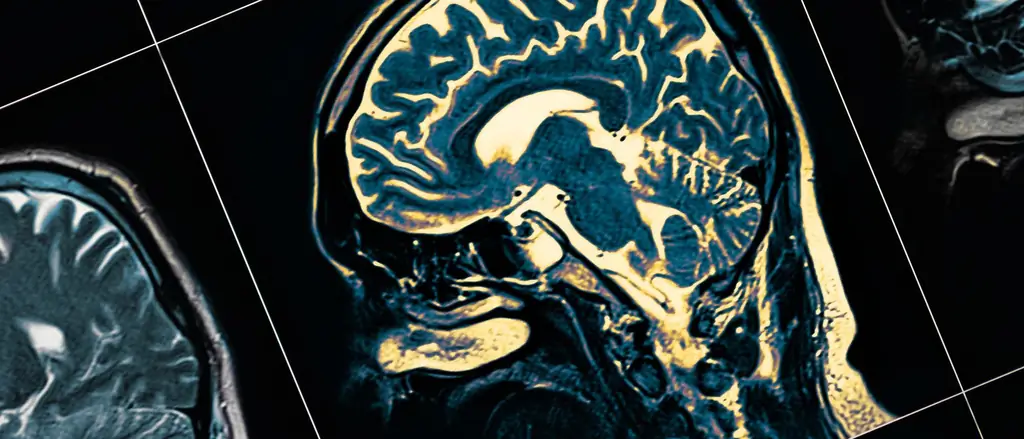

Ученая степень дает ряд преимуществ. Однако годы интенсивного обучения не могут остановить процессы старения в мозгу. Международная исследовательская группа под руководством Ларса Нюберга из Университета Умео в Швеции пришла к такому выводу на основе нескольких европейских лонгитюдных исследований. Как сообщают нейробиолог и группа в «PNAS», они оценили сканирование мозга примерно 2000 взрослых в возрасте от 30 до 90 лет, которые неоднократно проходили обследование на магнитно-резонансном томографе.

В качестве меры старения мозга исследователи использовали потерю объема мозга, связанную как с нормальными, так и с патологическими процессами старения, также известную как атрофия мозга. Как и ожидалось, изображения показали, что участки коры головного мозга с возрастом уменьшались в объеме. То же самое верно и для центра обучения и памяти мозга, гиппокампа: он сжимался примерно на 50 кубических миллиметров в год, что составляет около одного процента его объема..